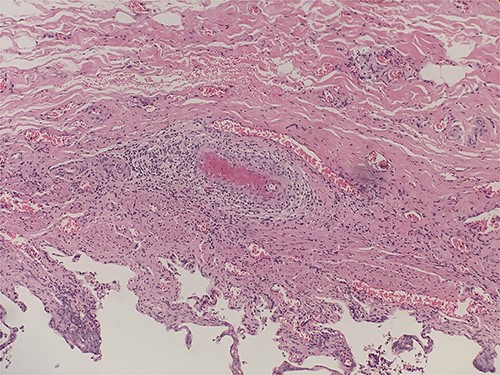

He underwent laparoscopic cholecystectomy under general anesthesia in the standard way. The gallbladder was found to be macroscopically inflamed with few omental adhesions. The procedure was completed peacefully, and the patient recovered well. The histology of the gallbladder specimen came back showing features of necrotizing vasculitis of small and medium arteries suggestive of PAN (Figs 1–3). He was treated with steroids for his systemic vasculitis and has shown significant improvement in his symptoms. His kidney function also markedly improved.

Low power view showing the mucosa of the gallbladder with multiple small and medium sized blood vessels shown by arrows (H&E 40X).